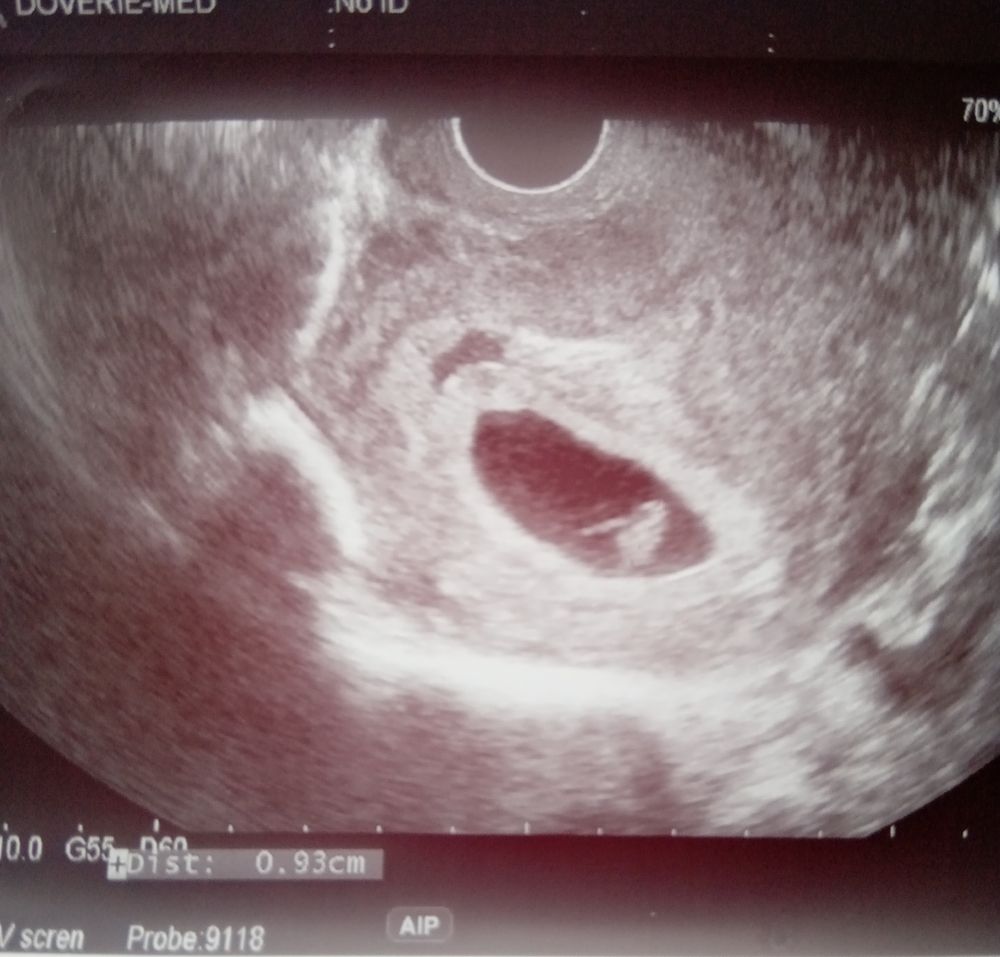

Субхориальная гематома

Вот это нижнее УЗИ было вагинально или по животу?

Олюшка78, обе фотки с одного УЗИ, вагинально. На ваше не похоже)))))